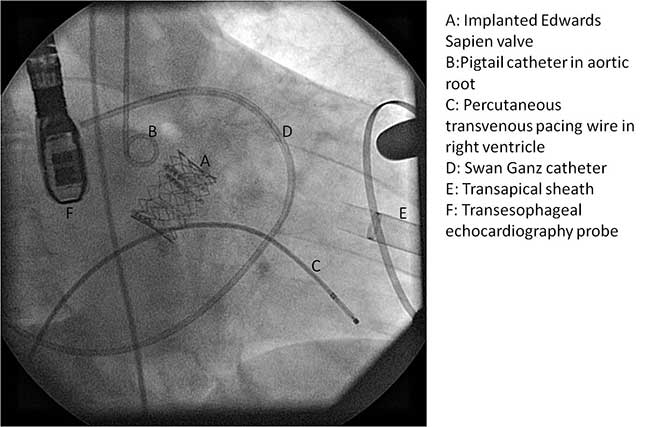

Transcatheter Aortic Valve Implantation: Anesthetic ...

Transcatheter Aortic Valve Implantation: Anesthetic Considerations 1454 Transcatheter Aortic Valve Implantation ANESTHESIA & ANALGESIA. aortic valve replacement with the corevalve revalving system. Echocardiography 2008;25:840–8 ... View Doc